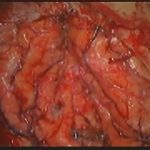

手術前2

摘出 中